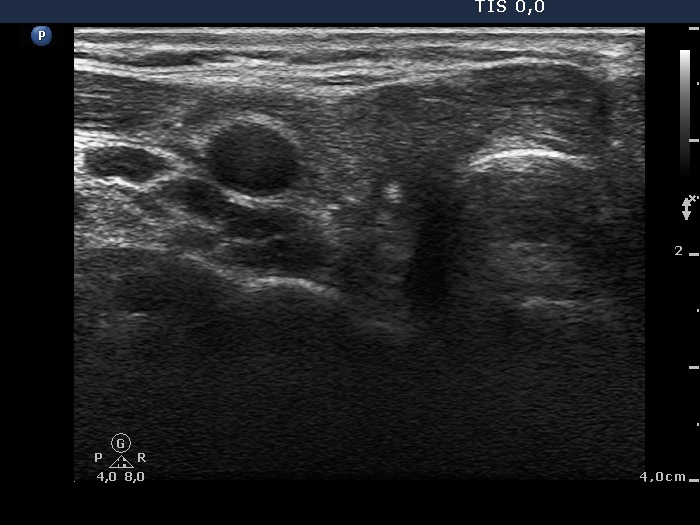

Five weeks after surgery (third row of images)

Ultrasonography. A moderately hypoechogenic mass with discrete circumscribed areas replaced the resected thyroid.

Taking the location and the morphology of the tumor into account we advised radioiodine therapy.